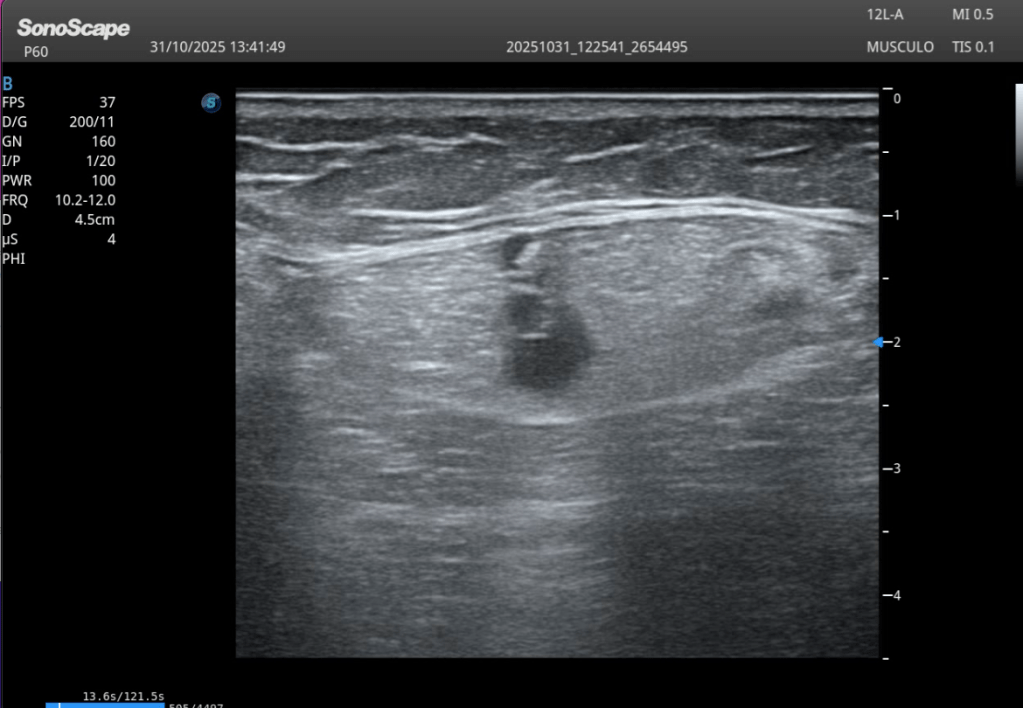

A nivel de la cabeza femoral izquierda, en la región profunda del psoas ilíaco, se identifica:

En eje longitudinal (eje largo – línea roja): Imagen anecoica alargada Localizada en las fibras profundas del psoas Con una longitud aproximada de 2,5 cm En eje transversal (eje corto – línea amarilla): La lesión se reproduce claramente, confirmando su existencia siempre en dos ejes. Si no lo veo en 2 cortes, no existe.

En este caso, la correlación clínica y ecográfica es directa.

Diagnóstico

Rotura de las fibras internas posteriores del psoas ilíaco izquierdo, con colección anecoica compatible con hematoma.